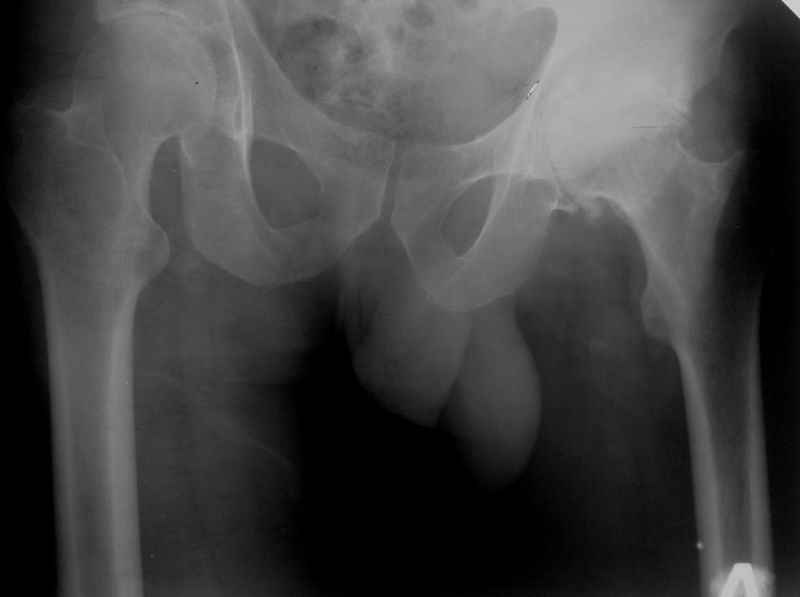

Хотелось бы увидеть рентгенограмму до имплантации. Погружение достаточное, хороший контакт с костным ложем. Центр вращения сустава сохранен. Мне кажется выбрана большая "чашка". Во всяком случае - не стоит ничего менять. Канзюба А.И.

Исходная рентгенограмма?

Исходная R- гр см. выше.